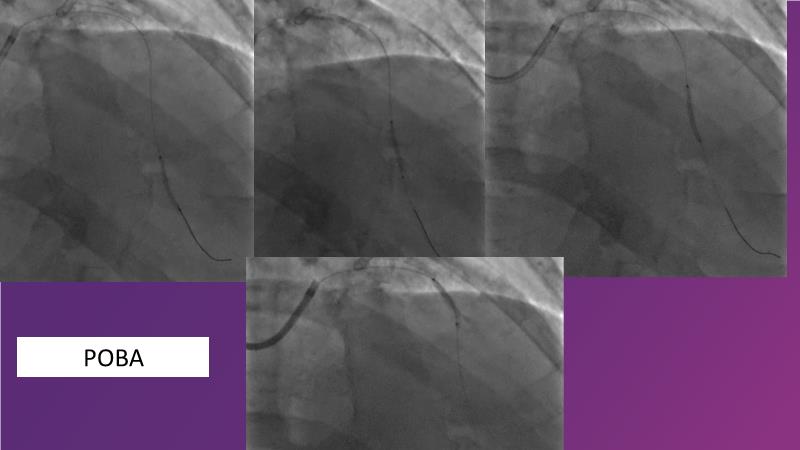

Sirolimus-coated balloon: exploring the case- and clinical-based evidences

Browse this EuroPCR 2024 session to explore the safety and efficacy of sirolimus-coated balloons from pre-clinical data, review MagicTouch data from real-world populations with case-based examples, and learn about the MagicTouch sirolimus-coated balloon clinical programs. Discover insights and takeaways from the significance of the EASTBOURNE subgroups, and analyze the challenges and opportunities in PCI for diabetic patients.

- To learn from the real world registries and complex cases to understand the practical implications and potential of the device in diverse patient population